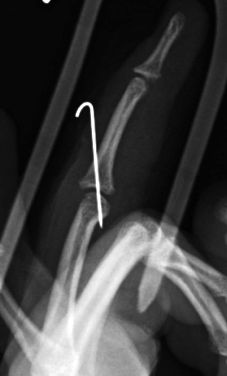

A. Fracturas de falange distal

Es importante diferenciar las fracturas extraepifisarias de las fracturas fisarias puesto que su manejo terapéutico es diferente. Las fracturas extraepifisarias son fracturas generalmente estables que se tratan con inmovilización durante 3-4 semanas con interfalángica proximal libre mientras que las fracturas fisarias desplazadas requerirán reducción de la fractura e inmovilización. Dentro de este tipo podemos encontrar, las llamadas “mallet finger” o dedo en martillo y la fractura de Seymour

Se trata de una deformidad del dedo con flexo de la falange distal por lesión del tendón extensor o un arrancamiento óseo en la base de la tercera falange. Es más frecuente en la adolescencia, aunque puede ocurrir a cualquier edad. El dedo en martillo tendinoso por rotura del extensor sin lesión ósea se trata con una férula con la IFD en extensión durante 8 semanas. Se debe realizar un tratamiento quirúrgico cuando existe fractura con un fragmento avulsionado superior al 40% de la superficie articular pudiendo realizar diferentes técnicas quirúrgicas. (Figura 19)

Figura 19: a, b- Fractura de la falange distal desplazada con avulsión tendón extensor. Tratamiento quirúrgico mediante técnica de Ishiguro